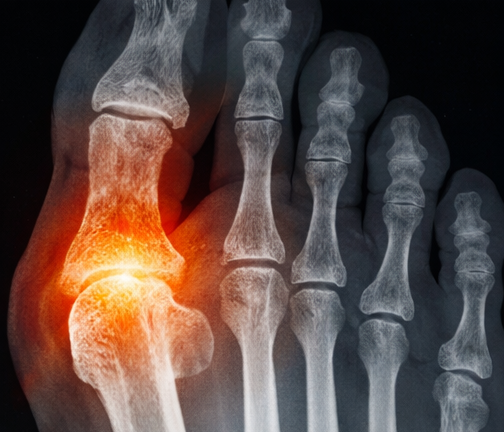

요산이 많아져 배출되지 못하면

통풍으로 이어질 수 있습니다!

배출되지 못한 요산이 혈액 속에 많아지면

작은 결정 형태로 뭉칠 수 있습니다.

이 결정이 관절 주변에 침착되면서 염증과 통증을 일으킬 수 있는데,

이것이 우리가 흔히 아는 *통풍입니다.